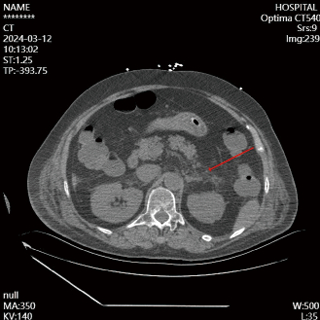

入院第4天,患者神志尚未转清,有自主睁眼,但对呼喊无反应,对疼痛刺激有局部屈曲反应,查体腹软,左上腹触诊患者有明显疼痛刺激反应,复查腹部CT(见图 2),提示胰腺体下方渗液明显增加,改良的CT严重指数评分(modified CT severity index, MCTSI)4分。动态复查血清淀粉酶及脂肪酶,尽管胰酶指标仍在正常范围,修正临床诊断:AP。调整治疗,在之前胃肠道功能支持治疗基础上,加用生长抑素抑制胰液分泌。治疗3 d后复查腹部增强CT(见图 3),胰腺无坏死,胰周渗液明显吸收,MCTSI 2分,逐步减停生长抑素。

| 图 2 2024-03-12患者胰腺下方见少许片絮状渗出影,范围较前(2024-03-09)增大 |